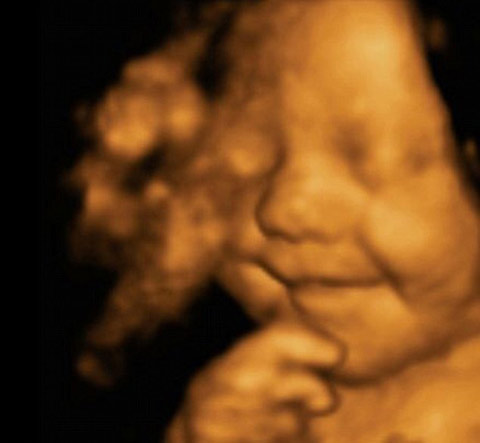

Grinning from ear to ear, this picture shows little Leo Hargreaves was rather happy with his world – even before he was born.

The remarkable image was taken from an ultrasound scan at 31 weeks.

The image is a 4D scan - increasingly popular with expectant parents to get a glimpse of how their child will look.

Rather then the grainy ‘flat’ images produced by the 2D scanners usually used by the NHS, a 4D machine stitches together pictures taken from a variety of angles to create clear three-dimensional images.

These are then recorded on video – the fourth dimension.